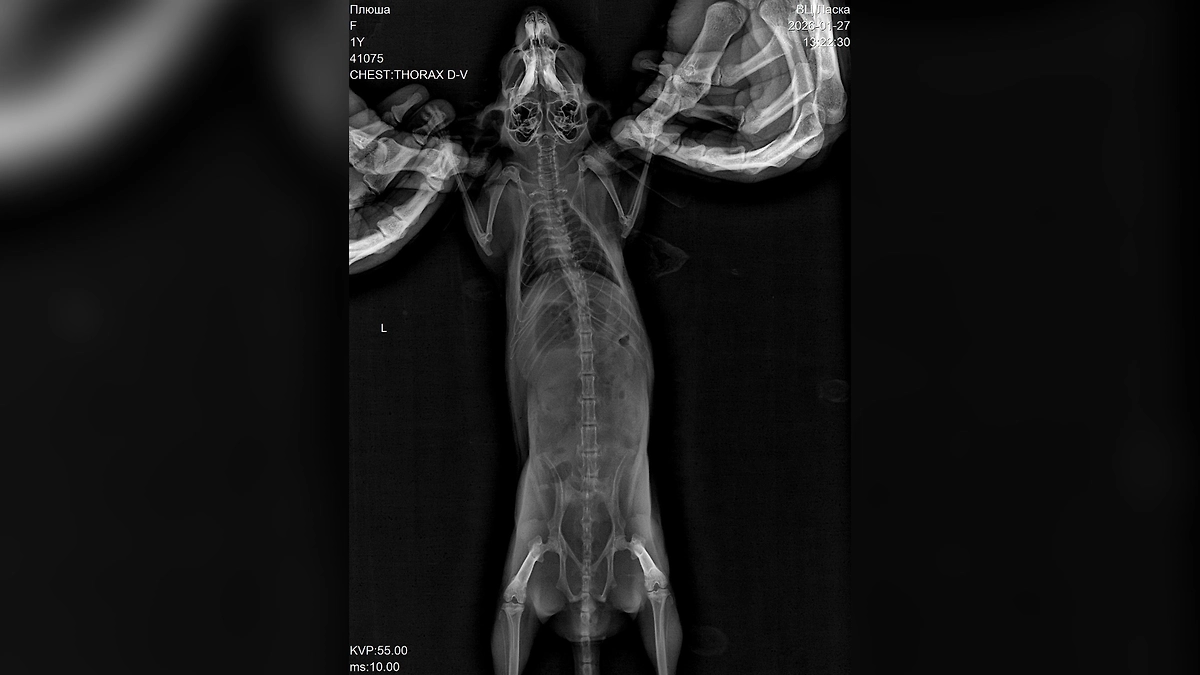

Пока хозяина не было дома грызун каким-то образом выбрался из своей клетки днём. Вечером Билан нашёл Плюшу возле музыкального оборудования, у неё была заметная рана на носу. Исполнитель немедленно связался с ветеринаром и получил инструкции по оказанию первой помощи, однако к утру состояние шиншиллы резко ухудшилось. Из-за сильного снегопада и пробок путь до клиники, находившейся в 60 километрах, занял почти два часа.

«За неё боролись около четырёх часов, но к сожалению, травмы оказались несовместимыми с жизнью. Диагноз — черепно-мозговая травма и отёк головного мозга», — написал он.

По словам Билана, он сначала предположил, что шиншилла могла получить травмы из-за кота Шахтёр, поскольку он хищник. Однако, по всей видимости, Плюша самостоятельно выбралась из клетки и с разбега врезалась в панорамное окно, что принесло тяжёлые травмы. Артист обратил внимание на то, как важно заранее понимать, с какими трудностями можно столкнуться, когда заводишь подобное животное.